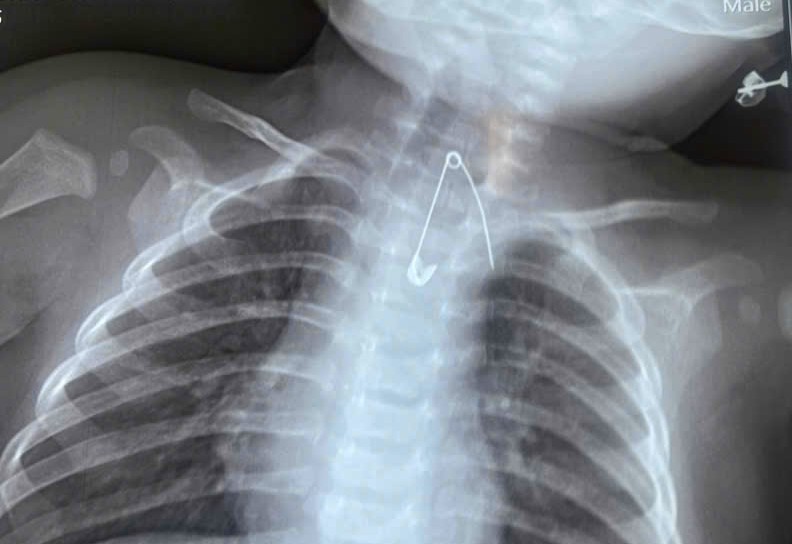

Safety pin in the esophagus of the 7-month-old boy. Photo: Hospital provided

Doctors at Ca Mau Obstetrics and Pediatrics Hospital discovered the pin during imaging scans on 8/1. It was embedded in the soft tissue of the upper one-third of the baby's esophagus, perilously close to the aorta. This foreign object posed a significant risk of severe damage to major blood vessels, leading to massive hemorrhage and life-threatening complications if not promptly addressed. Fortunately, a surgical team successfully intervened to safely remove the object.